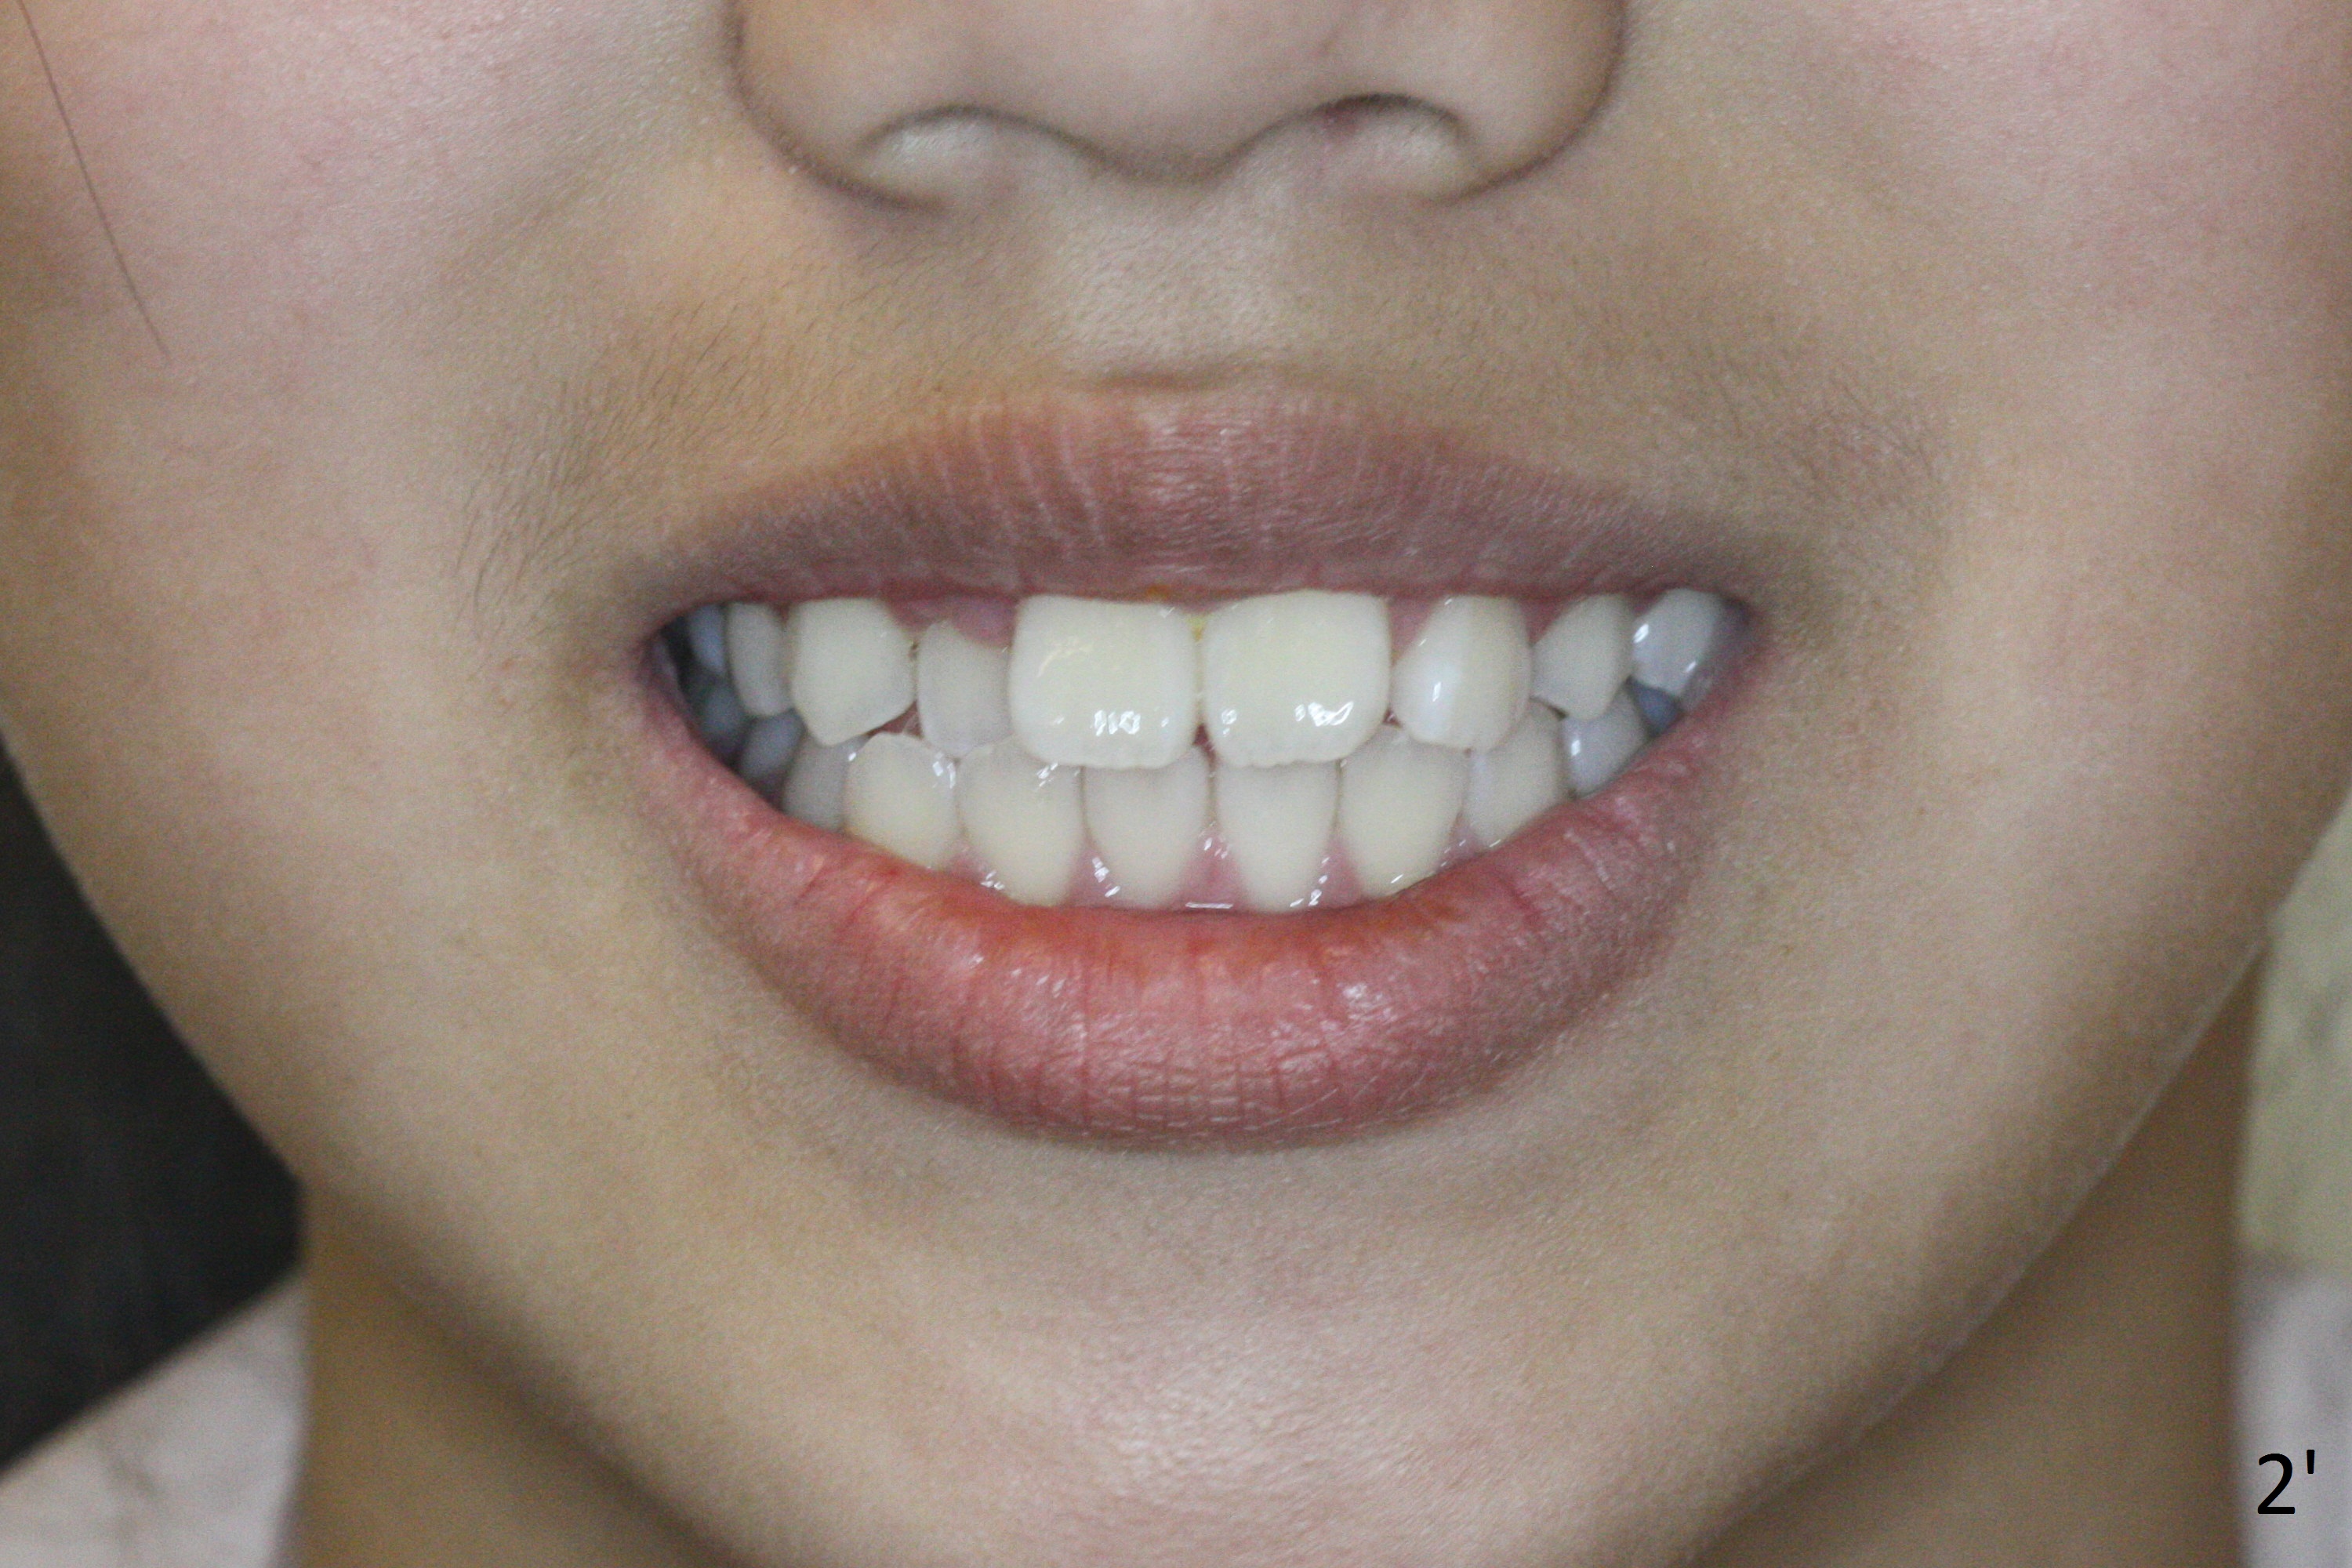

Two sisters (Sophia, 13 years old and Selina, 11) present to clinic for orthodontic treatment. Dental anomalies of Sophia include microdontia of the upper lateral incisors and congenital missing of the upper right permanent canine (Fig.5,6). For Selina, the upper right lateral incisor (Fig.5') and the upper left second bicuspid (Fig,6') are in cross bite.